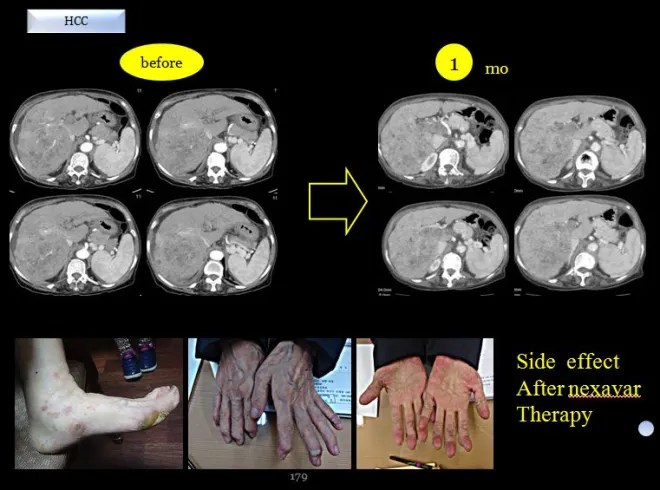

This patient was classified as a Taeeumin(Autumn type: in sasang typology) and was of advanced age. The liver cancer was detected at an advanced stage, with the right hepatic lobe almost entirely infiltrated by tumor, making transarterial chemoembolization infeasible. Sorafenib was therefore initiated. In my assessment, although sorafenib is a drug that aligns with the Taeeumin constitution, the patient experienced severe dermatologic adverse effects and discontinued the medication in less than one month.

The above image shows the actual side effects observed on the patient’s hands and feet by sorafenib (Nexavar)

Later, a collaborating physician requested constitutional classification, and I identified several Taeeumin patients. I was informed that, in those cases, the use of sorafenib led to very favorable outcomes. However, in this particular patient, severe dermatologic adverse effects affecting the hands and feet made continued use impossible, leading to discontinuation and subsequent presentation to my clinic.

As shown above, after approximately one month of sorafenib use, the tumor had progressed further, and there was extensive peeling of the skin on the hands and feet. The patient was over 70 years old, and at that time had severe ascites and pleural effusion. In my assessment, the prognosis appeared very poor, and survival was expected to be limited.